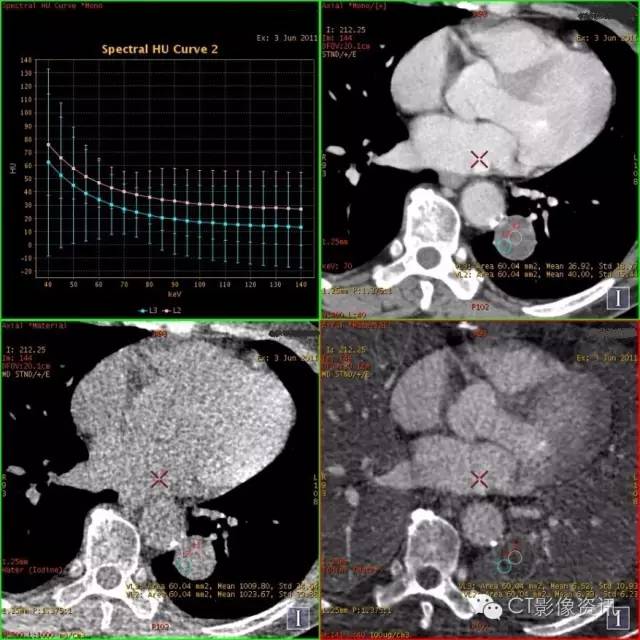

病例2

NIC结果:中央区0.37,周围区0.46

以上病例的λHU值结果

肺结节的能谱CT鉴别诊断要点 能谱衰减曲线:以静脉期明显; 在低KeV区差异明显; 速降型——恶性、炎性,缓降型——结核、良性,平台型(反向)——囊变坏死区、脂肪; 肺癌和炎性病变中央区的NIC值具有显著的差异,因此NIC值对鉴别肺结节良、恶性病变具有高敏感性与特异性; 肺癌和炎性病变的能谱衰减曲线斜率(λHU)具有显著的差异。